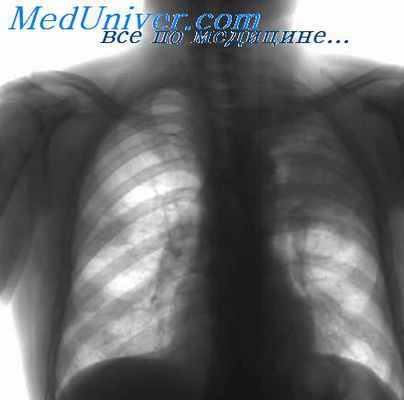

Туберкулезный менингит может начаться как острый менингеальный синдром или как медленно прогрессирующий процесс, приводящий к деменции. Для диагностики проводится внутрикожная туберкулиновая проба. Сопутствующий туберкулез легких, выявляемый по данным рентгенографии грудной клетки, чаще наблюдается у детей с туберкулезным менингитом, чем у взрослых. Классическими находками в ЦСЖ при туберкулезном менингите являются снижение уровня глюкозы, повышение концентрации белка и полиморфонуклеарный или лимфоцитарный плеоцитоз.

- Рентгенография грудной клетки.